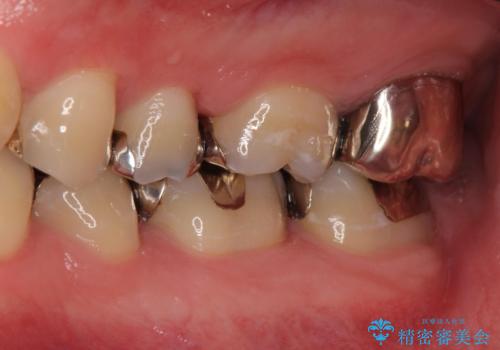

[e-maxインレー] 矯正治療前の虫歯治療

- 矯正治療前の患者様です。

う蝕があったのでe-maxインレーにて治療しました。

- e-maxインレー 7.7万円 費用は治療当時の料金となります

う蝕があるままで矯正を始めてしまうと矯正治療中にう蝕が悪化する可能性があります。矯正治療を行う前はう蝕や歯周病がある場合にはしっかり治療を行なってから矯正治療がスタートします。

![[e-maxインレー] 矯正治療前の虫歯治療の治療前](https://seimitsushinbi.jp/wp/wp-content/uploads/2023/08/IMG_1022-2-500x350.jpg?v=1691812242)